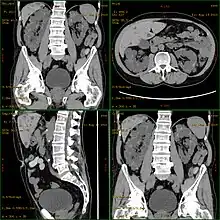

| Severely affected polycystic kidneys removed at time of transplantation | |

| Diagnostic method | MRI, CT scan, Ultrasound[1] |

Polycystic kidney disease can be ascertained via a CT scan of abdomen, as well as, an MRI and ultrasound of the same area.[23] A physical exam/test can reveal enlarged liver, heart murmurs and elevated blood pressure.[1]